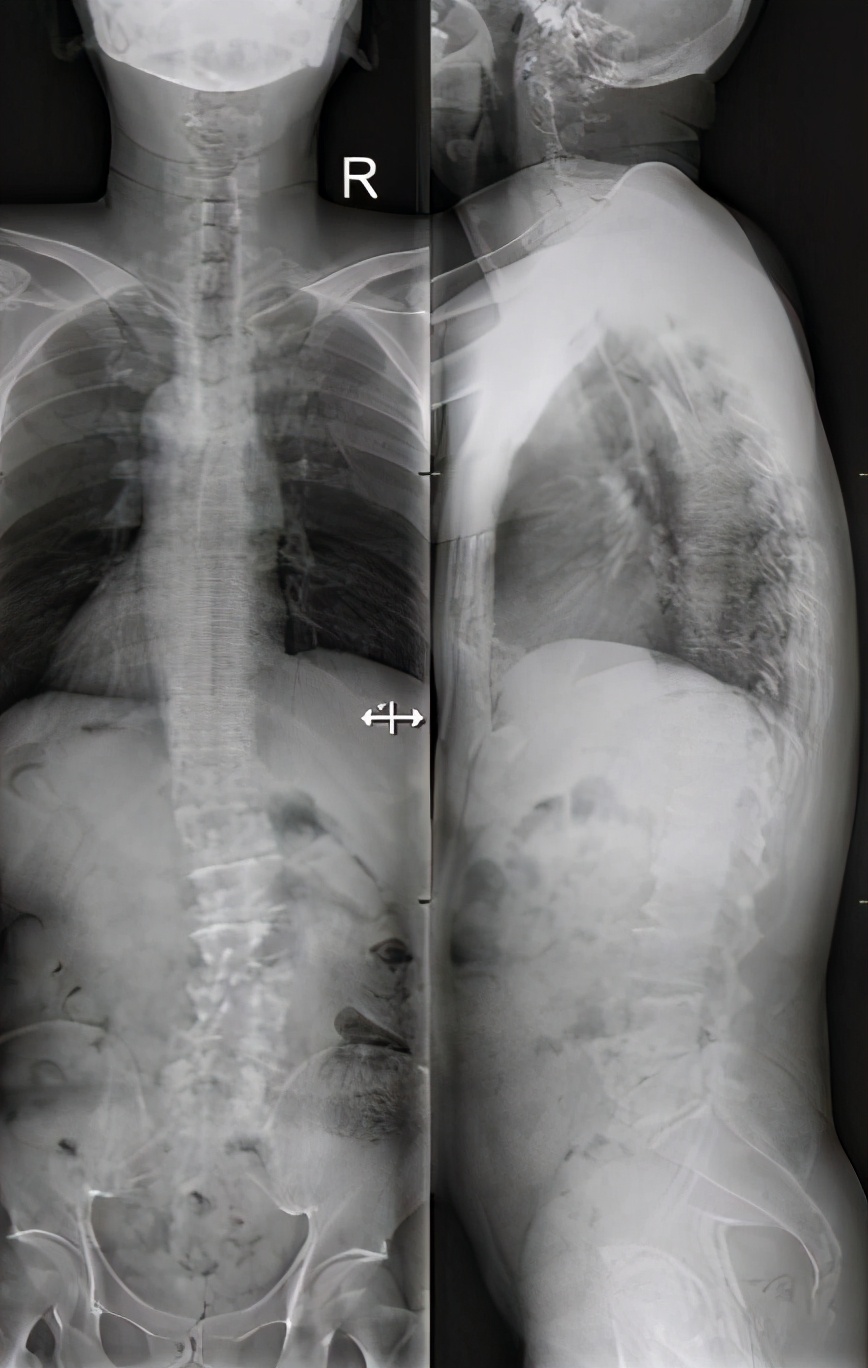

患者老年男性,因“腰痛伴有双下肢疼痛、麻木”入院,腰部疼痛为主。查体:间歇性跛行,腰背棘突及棘突间叩击痛,双下肢肌力降落。影像示:腰椎退行性变,腰椎向左侧突,椎体旋转,Cobb角为29.2°,腰椎诸椎间隙椎间高度减低,L1/2-L3/4及L5/S1椎间盘突出。患者接受胸、腰后路减压植骨融合内固定术。术后患者腰椎侧突矫正,术后Cobb角降低至10°。

患者男性,61岁,因“腰部沉重感伴双下肢疼痛、麻木2年加重2月”入院,查体:间歇性跛行,腰背棘突及棘突间叩击痛明显,左足肌力3级,右足肌力4级。影像示:腰椎退行性变,腰椎右侧突,Cobb角为26.7°,腰椎管狭窄,L4/5、L5/S1椎间盘突出。患者接受腰后路减压植骨融合内固定术。术后患者腰椎侧突矫正,术后Cobb角降低至7.8°。